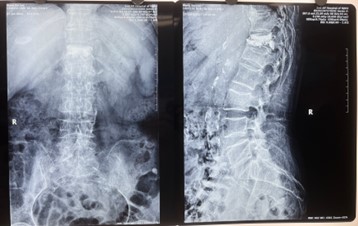

骨質(zhì)疏松是老年人經(jīng)常出現(xiàn)的一種全身性的以骨鈣流失為特征的自然退變,往往在輕微外力的作用下,很多患者僅僅由于打個噴嚏或者一個彎腰動作便會誘發(fā)椎體骨折。特別是胸腰椎壓縮骨折。胸腰椎骨折可造成局部疼痛,活動障礙,甚至引起下肢癱瘓,生活質(zhì)量明顯下降。另外,由于椎體壓縮,脊柱產(chǎn)生后凸畸形,胸腔及腹腔某些臟器受到壓迫,使呼吸、心臟和消化系統(tǒng)的功能出現(xiàn)障礙。

經(jīng)皮椎體球囊擴(kuò)張成形術(shù)是一種微創(chuàng)脊柱外科技術(shù),主要應(yīng)用于骨質(zhì)疏松癥的椎體壓縮性骨折,對減輕疼痛,增加椎體強(qiáng)度,改善全身相關(guān)癥狀,具有明顯的效果,甚至可以在一定程度上改善脊柱后凸畸形。

術(shù)中切口5毫米,在在C形臂X光機(jī)透視指引下,確定進(jìn)針的方向及進(jìn)針的深度,經(jīng)椎弓根向椎體置管,建立通道,插入骨擴(kuò)張器(球囊)。球囊擴(kuò)張恢復(fù)椎體高度,并在椎體內(nèi)形成空腔,確定骨水泥的注入劑量,并注入骨水泥觀察其擴(kuò)散情況,大大降低了手術(shù)風(fēng)險(xiǎn),縮短了手術(shù)時間。

C形臂X光機(jī)作為手術(shù)中的重點(diǎn)設(shè)備,能準(zhǔn)確定位,手術(shù)過程中即時觀看、即時做決策,在C形臂X光機(jī)的指導(dǎo)下,醫(yī)生能迅速、精準(zhǔn)確定患者手術(shù)的部位。從而極大縮短手術(shù)時間,提高手術(shù)效率和質(zhì)量,減輕患者痛苦,讓手術(shù)更加快捷且安全。

對比一些9英寸的平板C形臂,普愛醫(yī)療PLX119C大平板C形臂,30CM*30CM想(30CM*30CM)的成像范圍,一次性可成像5節(jié)腰椎,有效減少小視野C形臂難以一次性確定傷椎,可能需要進(jìn)行多次拍攝的問題,使得手術(shù)效率更快、更準(zhǔn)確。